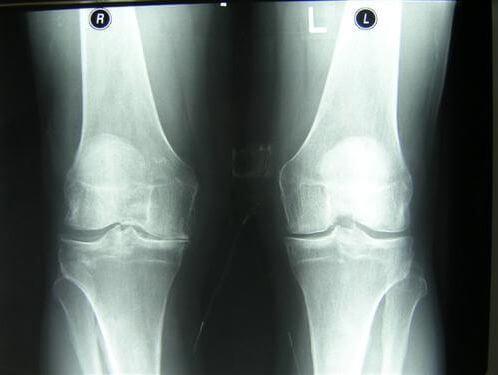

And here are pictures of joints before and after being treated with Maxiflex .

Woman. 54. The joint fully recovered.

Treatment period 1.5 months

Restoration of the elbow joint. Woman, 31. Maxiflex treatment duration - 2 months. The joint has fully recovered.

The photos clearly show that Maxiflex doesn’t just alleviate the pain,but also starts the processes of regeneration of the synovial fluid - the function chondroprotectors are meant to perform. As a result, the cartilage layer becomes wider and more elastic - the joint improves, pain and stiffness disappear.